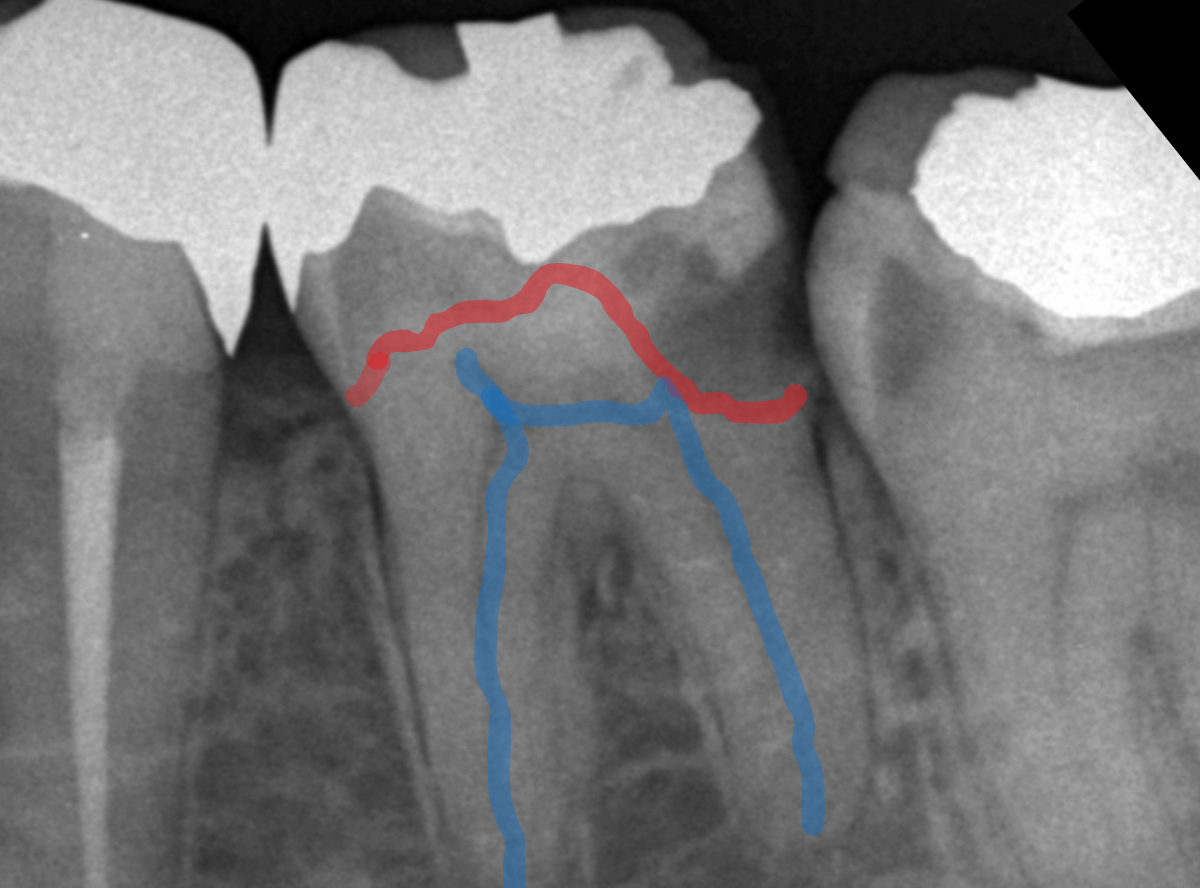

根尖性歯周炎とは、歯の根の先端に膿が溜まる病気のことです。

神経が死んでしまっていることがほとんどなので、歯髄炎ほど激しい痛みにならない事が多いですが、炎症が大きいと、歯髄炎に匹敵する痛みを生じたり、大きな腫れを引き起こすこともあります。

長い時間をかけて炎症が拡大しているため、根尖性歯周炎の治療は、長引く事が多いです。

治療は、歯の根の中を治療・消毒する根管治療を行います。

根尖病巣の大きさや炎症の程度はレントゲン写真でかなり判断できますが、必ずしも症状と一致しない事が多いのもやっかいなところで、「根管治療は難しい」とい言われる理由の一つです。